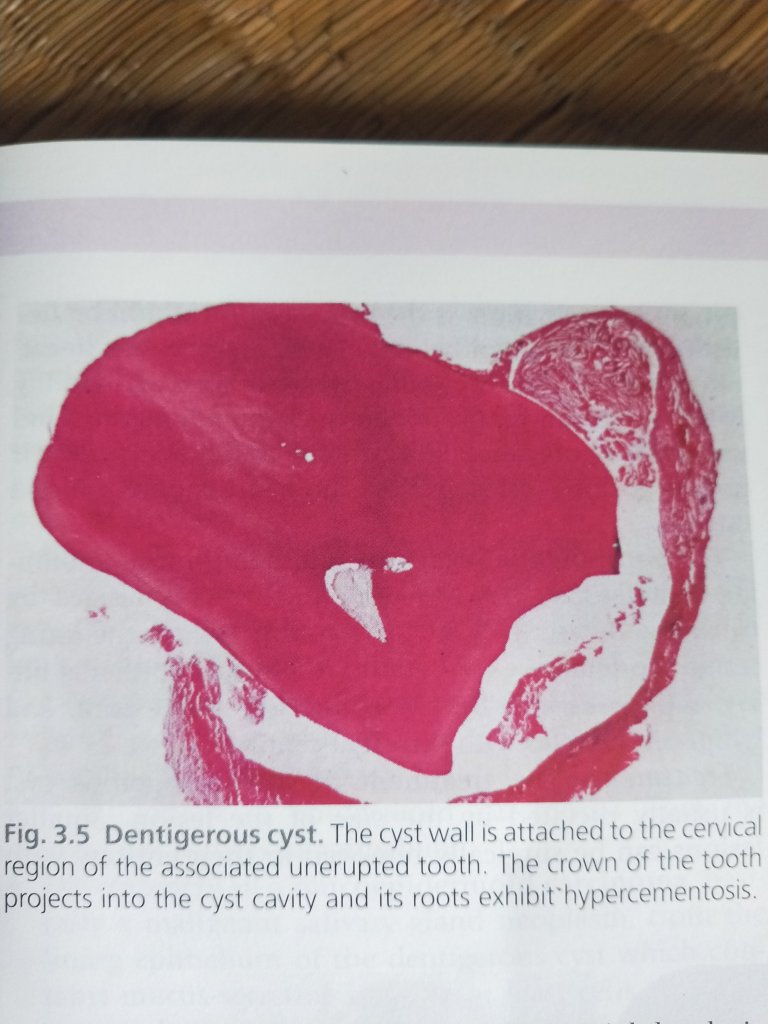

HISTOLOGICAL FEATURES

A. NON INFLAMMED TYPE:

- Lining derived from reduced dental epithelium, consists of 2-4 cell layers of non keratinized epithelium, without rete ridges.

- Wall composed of thin fibrous connective tissue appearing immature, as it is derived from the dental papilla.

B. INFLAMMATORY TYPE :

- Lining shows varying degrees of hyperplasia with rete ridges and occasionally even keratinization.

- Wall is composed of mature connective tissue which shows infiltration by chronic inflammatory cells.

- Focal areas of mucous cells can be seen in the lining. Small odontogenic epithelial islands can be seen in the wall.